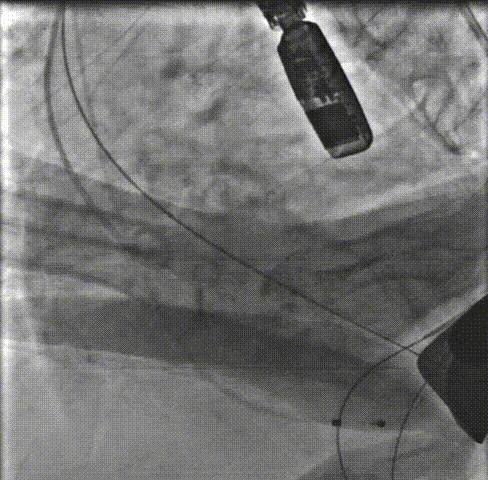

主动脉根部造影:主动脉根部造影可见主动脉瓣运动受限,伴有明显反流,瓣环平面上下可见大量团块状钙化。重度横位心。

预扩张:22mm球囊预扩后,患者出现室颤,电复律后转为窦性。

释放支撑臂:0位匀速释放Xcor-26瓣膜流出端。